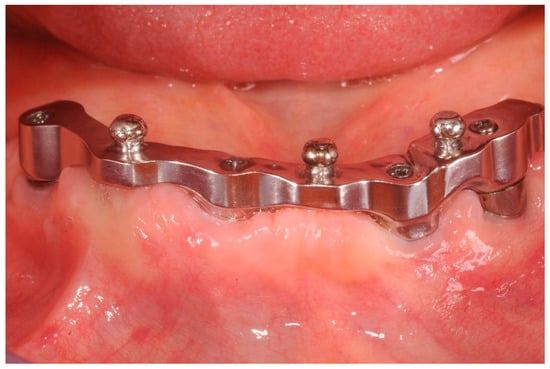

Figure 2.

Front view at three years follow up. Good hygiene maintenance and no inflammation of the keratinized mucosa.